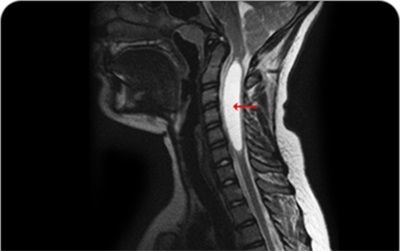

척수공동증 이미지. [사진=강남베드로병원]

척수공동증은 척수 내부에 뇌척수액, 세포외액 등의 액체가 고이는 공간(공동)이 생겨나고 점점 확장되며 척수 신경을 망가뜨리는 병이다. 이로 인해 척수신경이 손상되면 통증을 비롯해 이상감각, 감각 소실 등이 발생한다. 질환이 더 악화되면 연하 곤란, 근육 위축 및 사지 마비까지 이어지고 심지어 사망에 이를 수도 있다.

이에 자기공명영상(MRI) 촬영, CT 촬영 등을 통해 척수 내 공동을 확인하는 것이 첫 번째다. 또, 환자의 증상과 MRI에 나타나는 이상 현상의 관계를 살펴보는 과정도 함께 진행한다. 근전도 검사, 신경전도 검사, 신경계의 이상 유무를 판별하는 유발전위 검사 등을 함께 시행하기도 하며, 필요할 경우 뇌척수액 검사도 함께 시행한다.